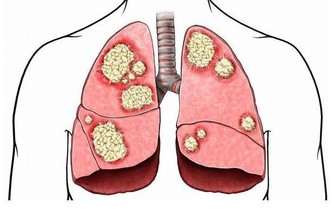

當我們談到有關女性的癌症類型時,你必然會提起乳腺癌,因為這是女性發病率最高的癌症。然而與此同時,大家一定不要忘了卵巢癌,這也是一名同樣危險的殺手,發病率也相當高。

而且,卵巢上皮癌死亡率,佔各類婦科腫瘤的首位。其死亡率如此之高,重要原因是很難早期發現。我們身邊會有一些女性知道對乳房進行自檢,卻不知道關注卵巢癌的跡象。

這其實也不能怪大家不重視,的確存在客觀原因,因為卵巢在身體深處,即使長了腫瘤也很難被感知到。即使身體用疼痛來提醒你,也往往會被當作普通的肚子痛。

那麼,卵巢癌都有哪些比較典型的症狀呢?很遺憾,並沒有那樣一個確定的信號,讓我們一看到就知道這個人患了卵巢癌。但好消息是,如果一名女性罹患卵巢癌,會有一個症狀比較突出,那就是“尿頻”,然而根據英國慈善機構的調查結果,大約只有百分之一的人知道經常需要排尿是卵巢癌的症狀。

原因很簡單,因為卵巢那里長了不該長的東西,也就是腫瘤,這個東西是有體積的,隨著它迅速長大,要獲取生長空間,就會去擠壓周圍的器官,包括膀胱。你的膀胱總是被壓迫,讓它誤以為自己需要尿尿。